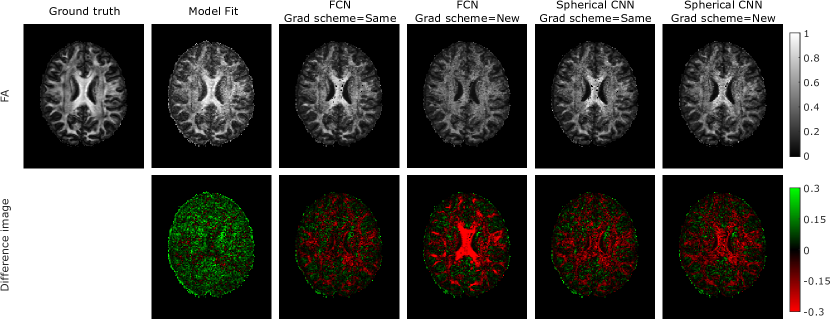

Qualitative and quantitative results of experiment 1 are shown in figures 2 and 3 respectively.

Figure 2 shows an example slice of a GT FA map from a test subject along with the model fitting, FCN and S-CNN estimations and error maps when the gradient scheme is the same or different between training and testing. When the training and testing schemes are the same FCN’s performance is consistent with the literature, estimating FA faithfully. When the gradient schemes are different the FCN estimates poorly. Estimation is especially poor in areas of high FA, such as the corpus callosum. S-CNN’s estimations are similar to the GT regardless of the gradient scheme. This shows S-CNN’s robustness to differing gradient schemes.

Figure 2: Results of experiment 1 are visualised on an subject unseen during training. Conventional fully-connected networks are compared against the S-CNN model at estimating FA with either the same gradient scheme as used in training or a new gradient scheme. The FCN shows a drop in performance when the gradient scheme is different between training and testing. The S-CNN doesn’t have this issue, therefore, it is robust to differing gradient schemes.